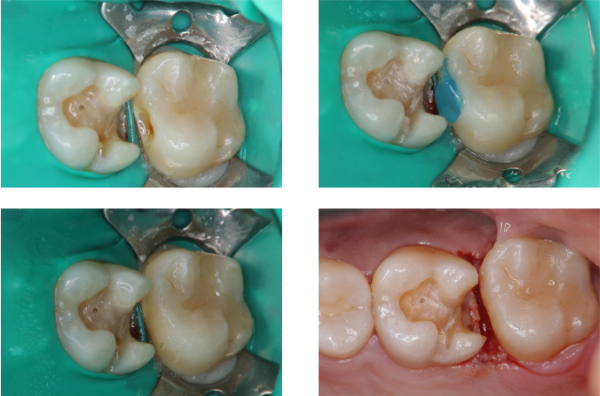

崁體製備,雷射牙齦修整

無殘膠存在

術前、術後比較